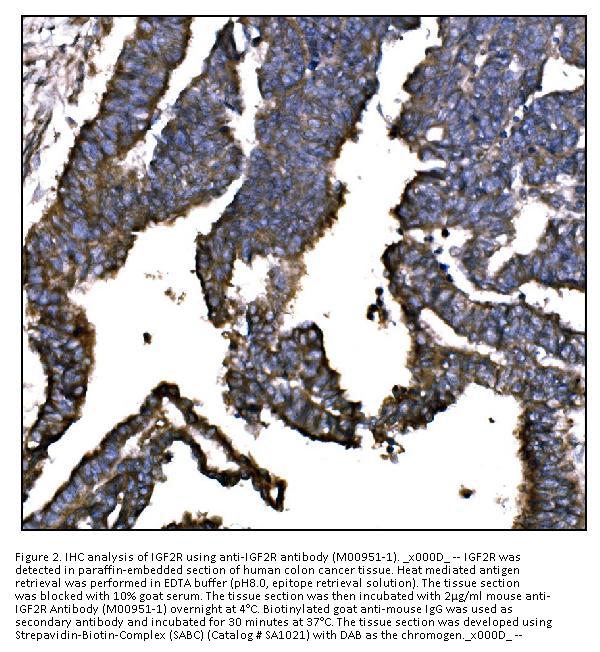

Immunohistochemistry (Paraffin-embedded Section), 2-5μg/ml, Human

E. coli-derived human IGF2R recombinant protein (Position: F424-R529).